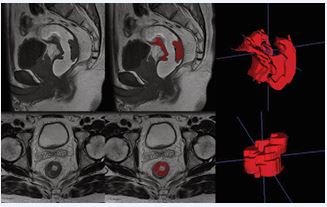

MRI images of enrolled patients were independently evaluated for routine radiologic features and segmentation of lesions outlined by one experienced radiologist and confirmed by another physician. Both physicians were unaware of the patient’s information and pathologic results, and when there was a disagreement between the two physicians’ results, the other senior radiologist reassessed them. Routine radiological features included (i) the location of the tumor, (ii) the TNM stage of the tumor, and (iii) the status of extra-mural vascular infiltration (EMVI) status. Images were imported into the open-source software ITK-SNAP (version 3.8.0, http://www. itksnap. org), and the region of interest was outlined layer by layer along the tumor margins in the Vaseline-perfused sagittal T1WI images and oblique axial T2WI images (Figure 2).

Figure 2 Schematic diagram of manually outlining lesions using ITK SNAP

The contents of the intestinal lumen and the uninvaded rectal wall were avoided as much as possible during the outlining process to ensure the accuracy and reproducibility of the outlining. The PyRadiomics package in Python 3.11.1 was used to extract 1,476 features from each software in T1WI and TWI, and the extracted imaging histology features mainly included three main categories: 1) first-order features; 2) morphological features; 3) grayscale features, gray-level co-occurrence matrix (Grey-Level Co-occurrence Matrix, GLCM) features, Grey-Level Dependence Matrix (GLDM) features, Grey Level Run Size Matrix (GLRLM) features, and Grey-Level Size Zone Matrix (GLSZM) features (Figure 3).